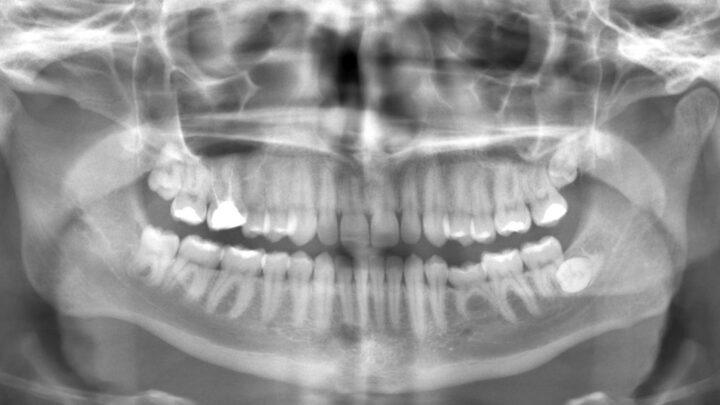

O que é radiologia odontológica? A radiologia odontológica é de suma importância para saúde bucal. Ela é a forma mais…